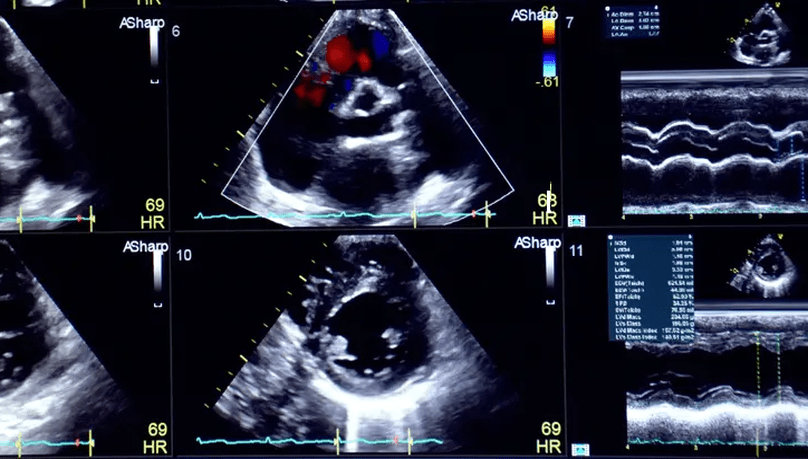

Color Doppler services refer to medical imaging procedures that use a technique called color Doppler ultrasound to visualize and assess blood flow within the body.

Echocardiography, often referred to as an “echo,” is a medical imaging technique that uses sound waves to create detailed images of the heart.